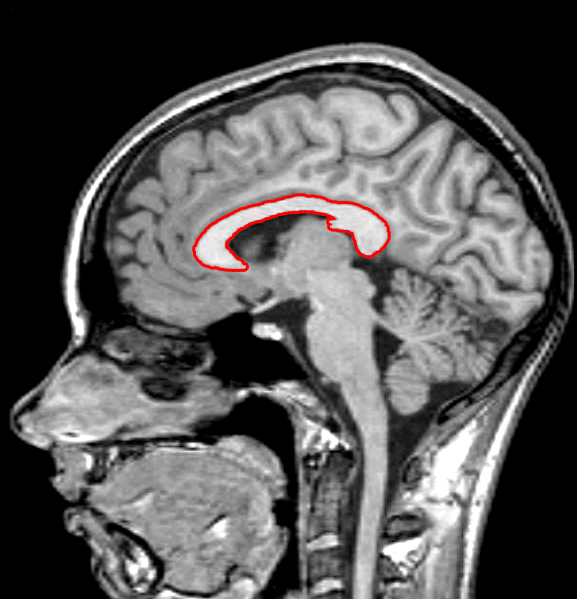

Sagittal brain MR image showing different parts of the corpus callosum …